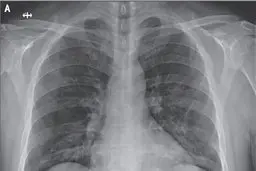

کرونا چه بلایی بر سر ریهها میآورد؟

کروناویروس به خاطر وجود شاخکهای تاجی شکلی که بر روی…